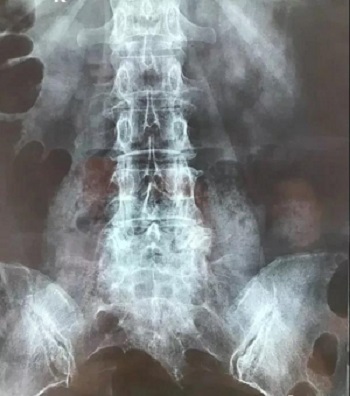

十、因此需要将磁共振的一张片子,进行分区域局部放大拍摄,尽可能的将片子上的细节拍摄清楚,将一张磁共振片子进行分区。

十一、将分区的磁共振图像,按顺序进行拍摄,即可获取如下比较有价值的清晰图片